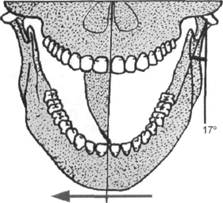

Смещение оси суставной головки вниз и вперед в сагиттальной и вертикальной плоскостях при перемещении нижней челюсти вперед и максимально вниз образует путь, характеризующийся расстоянием и траекторией, имеющей вид кривой, которая образует с франкфуртской плоскостью угол суставного пути. При движении нижней челюсти в сторону на стороне сократившейся латеральной крыловидной мышцы суставная головка с диском скользит по суставной поверхности суставного бугорка вниз, вперед и несколько наружу. Передневнутрен-нее смещение мыщелка в сторону глазницы по отношению к сагиттальному суставному пути составляет угол, описанный Беннетом и названный его именем. В среднем он равен 17° (рис. 13.31).

Кривая суставного пути, угол суставного пути и угол Беннета находятся в прямой зависимости от анатомического строения и функции ВНЧС.

Для записи и измерения суставного пути используют различные методы.